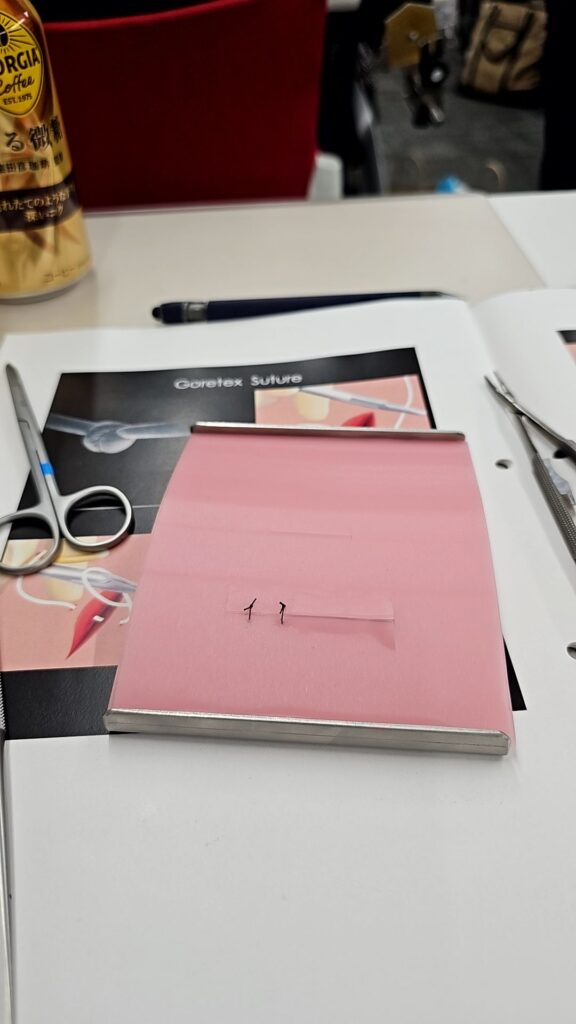

今回は歯周病の原因論や治療へのアプローチ、記録の取り方、歯周外科処置の選択、扱う器具、歯周外科処置での切開と縫合の講義と実習をしてきました。

大学生の時に使ったことがある実習道具を久しぶりに使い、基礎的な縫合と、縫合糸の種類別の縫合のやり方を実習しました。

また、竹内先生の症例の写真解説と動画を見た後に歯周外科手術の実習を模型を使って行ないました!